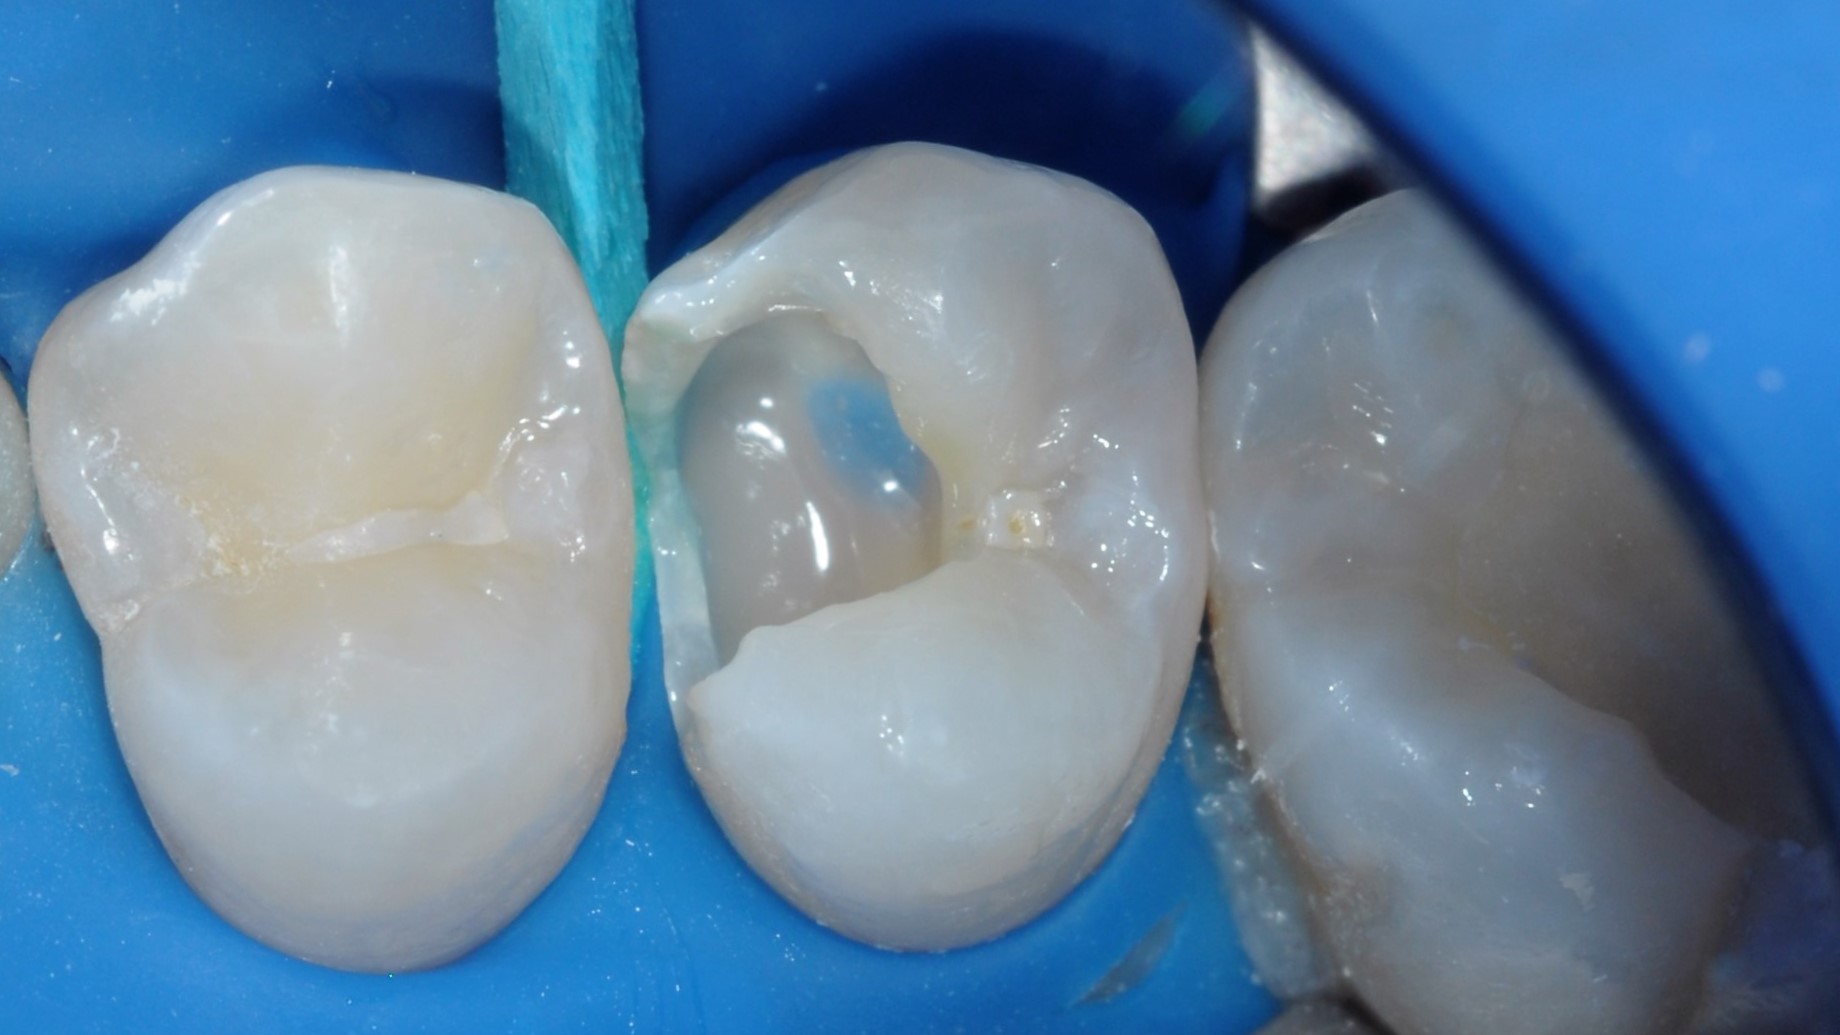

W celu zwiększenia konwersji monomeru w dnie ubytku, przeprowadzono dwa cykle polimeryzacji (Valiant LED, VISTA USA), rozdzielone chłodzeniem zęba powietrzem ze strzykawki wodno-powietrznej (3, 4). W celu zabezpieczenia warstwy hybrydowej na resztę zębiny zaaplikowano materiał kompozytowy typu flow o zwiększonej ilości napełniacza Clearfil Majesty ES Flow Super Low w kolorze A2 (Kuraray Noritake). Do wysokości niepodpartego szkliwa na powierzchni mezjalnej zrąb zębinowy odbudowano materiałem kompozytowym typu bulk fill – OliBulk Fill MD (Olident) (ryc. 6). Ze względu na nietolerancję długich zabiegów przez pacjenta, spowodowaną trudnościami w oddychaniu w pozycji leżącej, ubytek zaopatrzono materiałem tymczasowym (Cavit, 3M) i odroczono ostateczną odbudowę.

Ryc. 6. Wypełnienie zrębu zębinowego do wysokości niepodpartej listwy szkliwnej kompozytem płynnym typu bulk-fill OliBulk Fill MD (Olident).